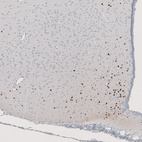

Immunohistochemical staining of human lung tumor (typical carcinoid) shows strong nuclear positivity in tumor cells.